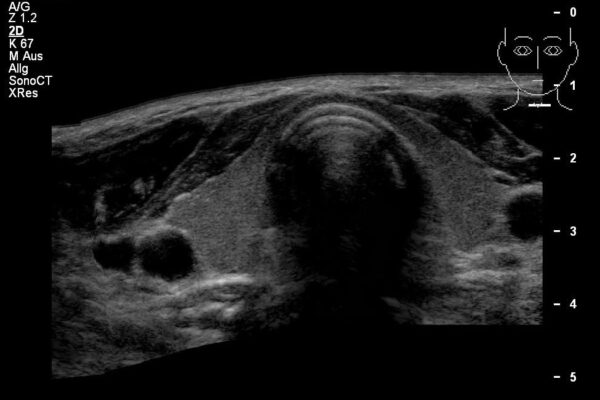

Die small parts sind eine sehr inhomogene Gruppe von Organen oder Weiteilveränderungen. In dieser Gruppe finden sich oft Untersuchungen der Schilddrüse, der Lymphdrüsen, der weiblichen Brust, der Hoden oder der Haut/Unterhaut.

Häufige Indikationen für Ultraschalluntersuchungen der small parts:

- Weibliche Brust: Tastbefund oder Schmerzen.